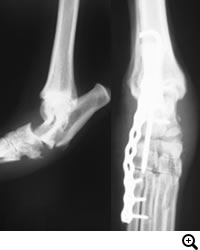

足根関節脱臼 / 不安定症

足根関節脱臼 / 不安定症とは

落下やジャンプに伴って起こる靭帯の損傷や免疫介在性関節炎、糖尿病・クッシング症候群など内科疾患に関連して起こる靭帯の変性などによって生じる足根関節の不安定性。

治療

外科適応の場合は全関節固定術、部分関節固定術、スーチャーアンカー法などをおこない、足根関節を固定します。